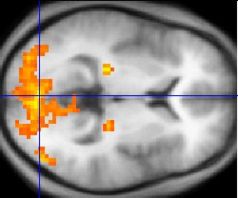

Functional MRI